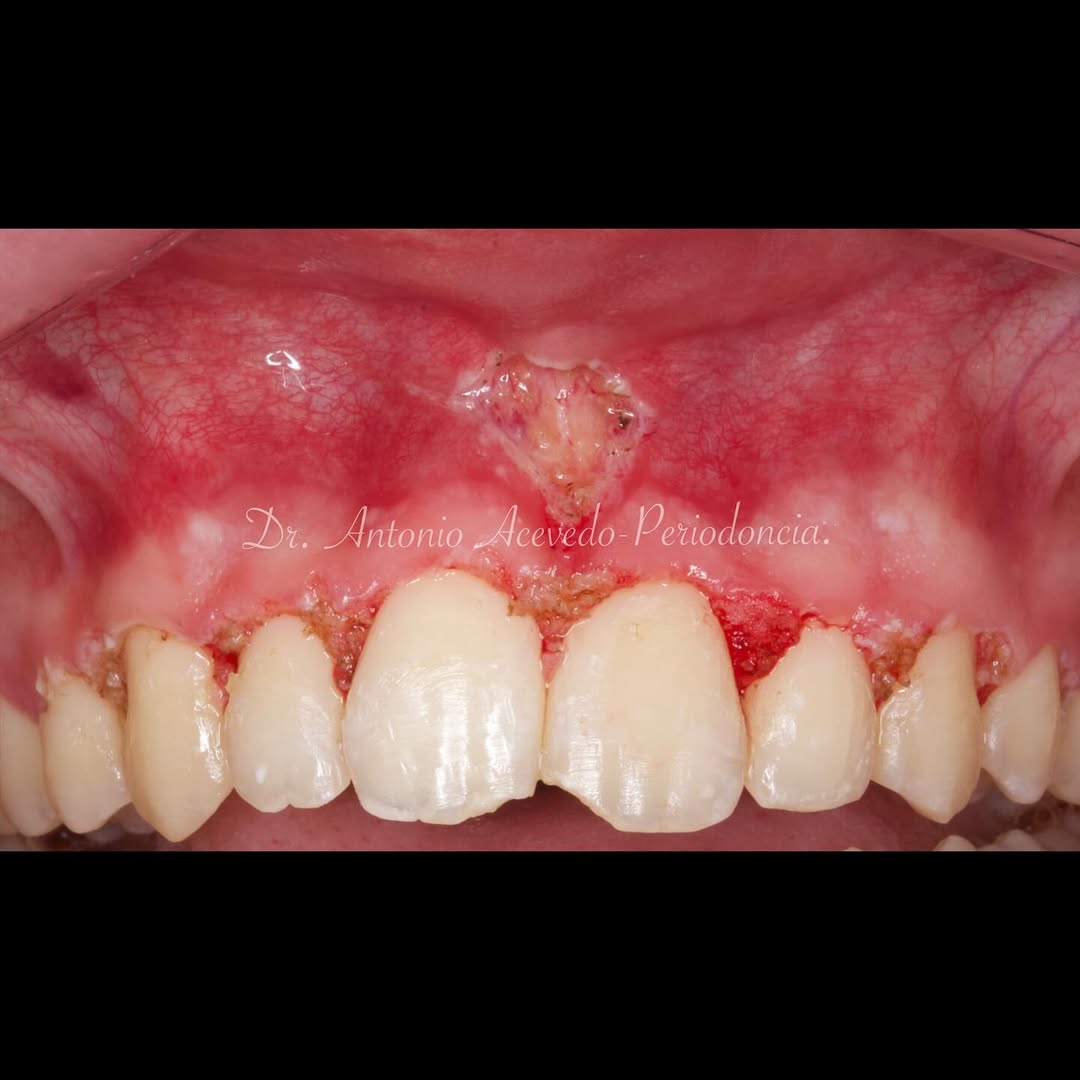

Durante una mañana, asistirás a una Cirugía Mucogingival de recubrimiento radicular de recesiones múltiples en IV y V sextante (36 a 43).

Gracias al uso del microscopio y a la proyección en tiempo real en pantalla, verás exactamente lo mismo que veo yo durante la cirugía, sin tener que estar

Aprende la planificación y técnica de la cirugía Mucogingival para el recubrimiento de recesiones y aumento de banda queratinizada en el sector anteroinferior

Una estancia clínica pensada para quienes quieran iniciarse o dar un paso más en el campo de la cirugía mucogingival. Durante esta experiencia tendrás la oportunidad de aprender en directo cómo se planifica y se lleva a cabo una cirugía mucogingival mediante técnica de Túnel.

La sesión